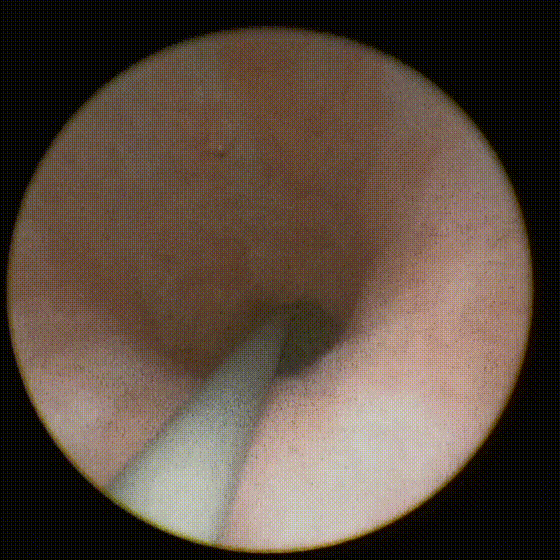

吴女士术后输尿管镜检查